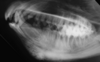

Q

What is shown in these images?

A

oral neoplasia in the left maxilla:

-missing I3 tooth

-displacement of I1 and I2 teeth

-large area of lysis surrounding left upper canine and extending rostrally